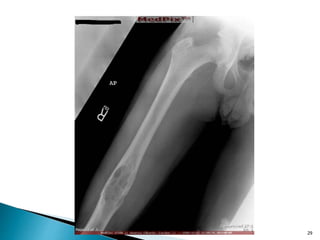

26

27

DR.KIRAN KAILAS

28